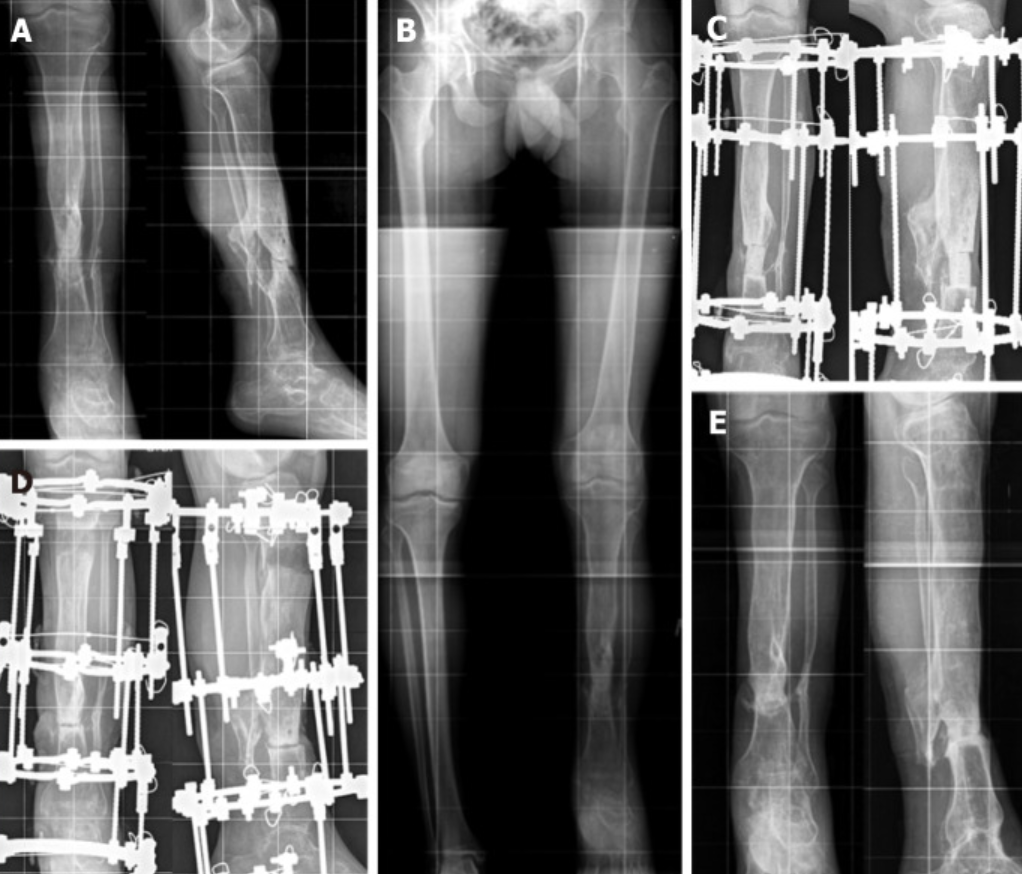

二、 骨缺损治疗:Masquelet 技术 vs. 骨搬移技术

对于创伤或感染导致的大段骨缺损,Masquelet 技术(诱导膜技术)与 Ilizarov 骨搬移技术仍是两大主流方案,目前的研究致力于对比二者并推动内固定搬移的发展。

• 疗效对比:系统评价显示,在治疗临界尺寸的骨缺损和感染性胫骨骨不连时,Masquelet 技术和骨搬移技术在总体愈合率和并发症方面无显著差异。但骨搬移技术在骨 ASAMI 评分上表现更好,且残余畸形的发生率较低,同时能显著减少重大非计划二次手术的次数。

• 内置骨搬移髓内钉:使用磁力驱动的骨搬移髓内钉治疗胫骨节段性缺损成为一项创新,虽然由于冶金问题面临市场撤回,但其初步临床系列报道显示了良好的骨愈合指数(约 37-41天/cm),避免了长期佩戴外固定架的痛苦。

• 钢板辅助骨段搬移(PABST):该技术通过内置延长钉结合钢板进行骨搬移,患者可在 8.7 个月内实现完全负重,93%的患者新生骨达到固结。结合滑轮和线缆的内部传输系统也正在开发中,以进一步减少对外部针的依赖。